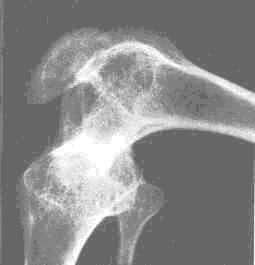

3. 骨質疏松癥:維生素 D 營養(yǎng)狀況差和鈣攝入量低是骨質疏松和骨折發(fā)生的重要危險因素。其特征為骨密度降低、骨骼微觀結構破壞,骨骼疼痛、骨折風險增加。

【科普】維生素 D 到底要不要補?